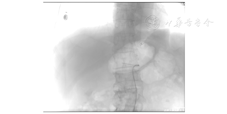

入院第2天,患者突然解黑便,量约500 mL,立即给予PPI抑酸、静脉注射尖吻蝮蛇血凝酶(商品名为苏灵)止血等治疗,行急诊胃镜检查,发现胃角和十二指肠球部溃疡(图3)。急查血常规示血红蛋白为118 g/L,故考虑消化性溃疡引起黑便可能性大,遂继续给予PPI、尖吻蝮蛇血凝酶等治疗,密切关注病情变化。入院第3天,患者出现鲜红色血便,量约2 000 mL,伴头晕、心慌,无腹痛,血压为86/60 mmHg,由于大量鲜血便,考虑为下消化道出血,立即在积极抗休克、PPI抑酸、输血、心电监护下行急诊肠镜检查,由于肠腔大量积血,影响视野,未发现出血点。遂又进行腹腔血管造影检查,发现右侧肝动脉分支造影剂蓄积,考虑假性动脉瘤,除此之外未发现造影剂流入肠道,见图4。经过全院会诊,考虑患者存在胆囊结石、胆囊炎等基础疾病,现出血原因不明,经积极保守治疗仍未控制出血,有外科手术指征,遂于11月21日行剖腹探查术,术中探查胃、小肠未见明显异常,胆囊壁增厚,并与结肠紧密相连,胆囊周围大量瘢痕组织增生,切开胆囊,可见大量血凝块,清除血凝块可见胆囊床侧胆囊内壁血管搏动性出血,缝扎胆囊内壁出血动脉,继续探查见胆囊与结肠肝曲形成内瘘,血液经瘘口流入肠腔,仔细分离胆囊结肠瘘(cholecystocolonic fistula, CCF)壁,常规切除胆囊,用可吸收线间断缝合关闭结肠瘘口,在距盲肠约25 cm末端回肠处行回肠双腔造口,腹膜、腹外斜肌腱膜、皮肤分别与肠管和肠系膜固定,0.9%氯化钠溶液清洗腹腔,放置引流管,清点器械、纱布无误后,关闭腹腔。术后病理诊断为CCF或慢性胆囊炎伴急性发作(图5)。患者术后恢复良好,随访至截稿日期,患者再无消化道出血表现。